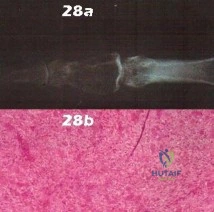

- Enchondroma

- Osteoblastoma

- Giant cell tumor

- Aneurysmal bone cyst

- Fibrous dysplasia

- Chondrosarcoma

- Periosteal chondroma

- Periosteal osteosarcoma

- Dysplasia epiphysealis hemimelica